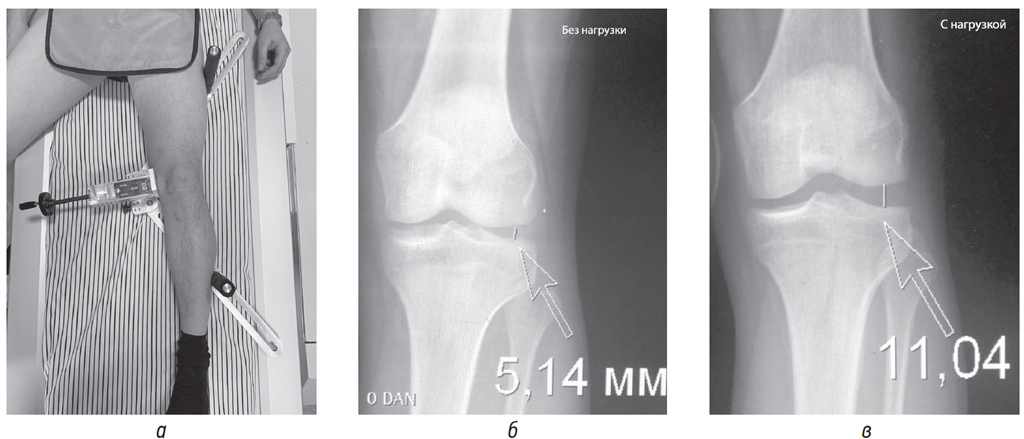

Всем пострадавшим с повреждением ЗЛУ клиническое обследование дополняли рентгенографией коленного сустава в стандартных проекциях, прямой рентгенографией с опорной нагрузкой, функциональной рентгенографией при сгибании под углом 150°, а также магнитно-резонансной томографией коленного сустава. Пациентам основной выборки функциональную рентгенологическую оценку вида и степени выраженности его варусной нестабильности выполняли по предложенной методике с применением разработанного на кафедре устройства (рис. 2, а–в).

Рис. 2. Функциональная рентгенография коленного сустава с аппаратно задаваемой варусной нагрузкой: а) внешний вид ко-нечности с устройством для функциональной рентгенографии; б) рентгенограмма коленного сустава в прямой проекции без нагрузки; в) рентгенограмма коленного сустава в прямой проекции с нагрузкой при повреждении ЗЛУ

По нашему опыту при функциональном тестировании разница между здоровым и пострадавшим суставами в раскрытии суставной щели ≥3 мм свидетельствовала о полном разрыве только МбКС, ≥4 мм — о разрыве МбКС и ЗЛУ, а ≥8 мм — о тотальном разрыве ЗЛУ и повреждении крестообразных связок.